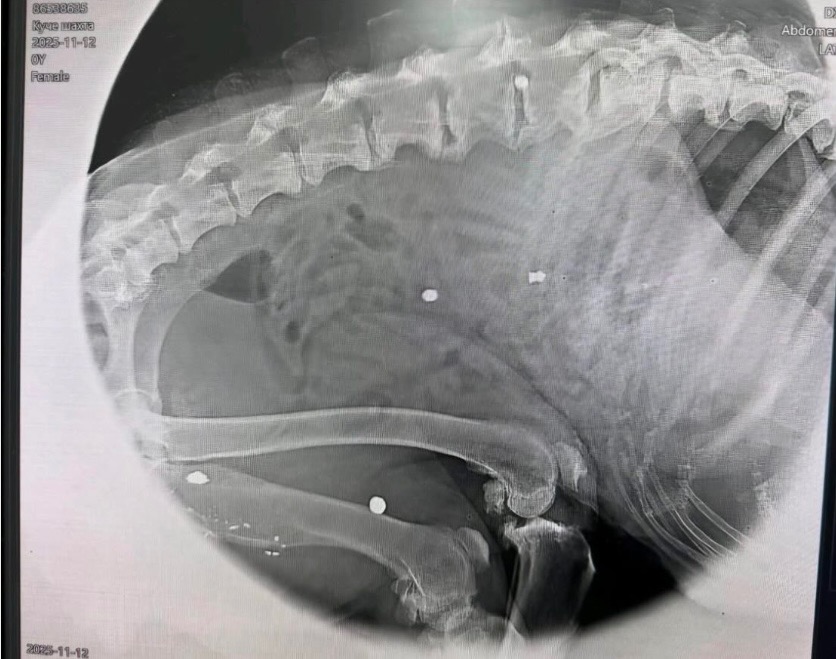

Die Hündin wurde mehrfach angeschossen, schwer verletzt gefunden und kämpfte anschließend in einer Klinik in Sofia/Bulgarien um ihr Leben. Sie war trächtig, doch ihre Welpen überlebten nicht. Neige selbst blieb gelähmt zurück und ist inkontinent. Trotz allem zeigt sie eine beeindruckende Lebensfreude und einen starken Willen zu leben.